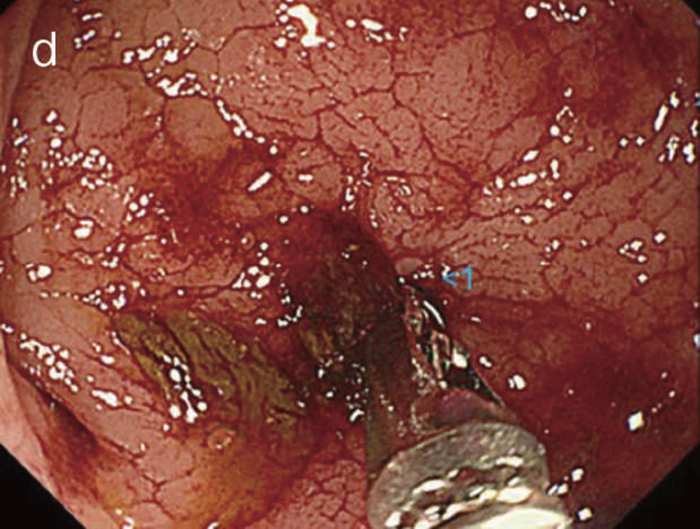

内視鏡検査による存在診断における課題は,CD関連消化管腫瘍を疑う所見の拾い上げになる。直腸肛門管領域に絨毛様の表面構造を有する病変を認めることが多い(図26)が,分化度の低い病変の拾い上げに有用な内視鏡所見はわかっていない1,3)。特に内科的治療で炎症の消退が困難な慢性に炎症が持続する領域の場合,炎症により腫瘍性病変を疑う所見の拾い上げがさらに困難となる。

図26 痔瘻一次口から表出したクローン病関連腫瘍の直腸反転内視鏡観察像

粘液をともない,腫瘍性病変を強く疑う表面構造を有している。当初の生検病理診断は過形成性病変で,再検の後,直腸切断術を施行した。(文献1)から転載)